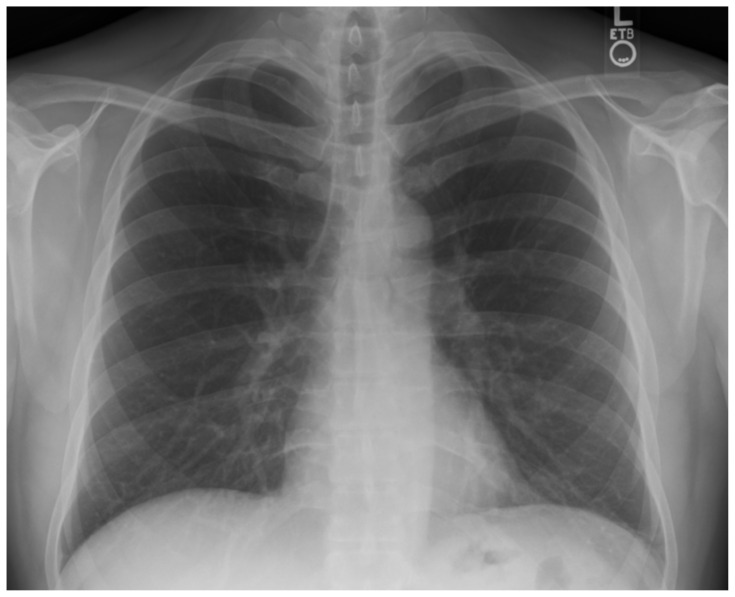

Abstract Image